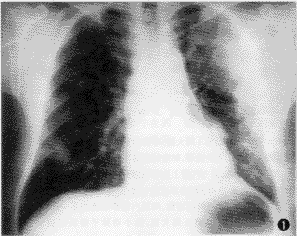

第38例——左肺大片融合阴影、右肺多发类圆形结节影